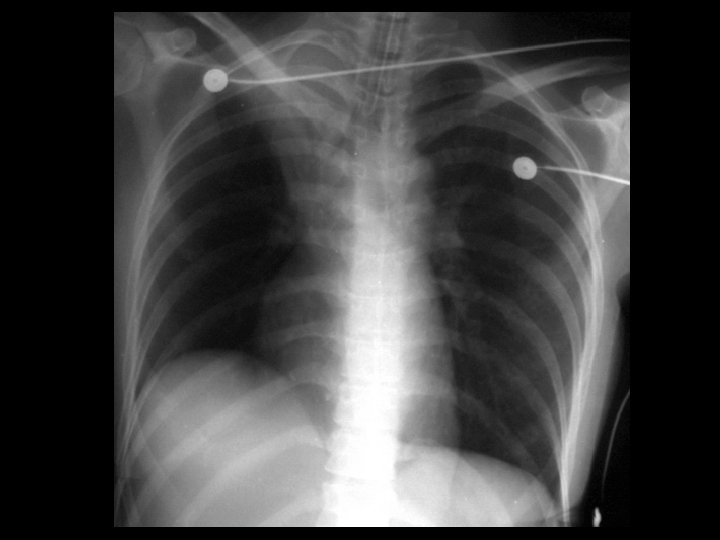

Swyer-James syndrome • Findings: – Hyperlucent left lung – Diminished pulmonary parenchymal and vascular markings – Expiration view shows air trapping • ddx: – Endobronhial foreign body – Pneumothorax – Congenital lobar emphysema – Pulomary artery hypoplasia